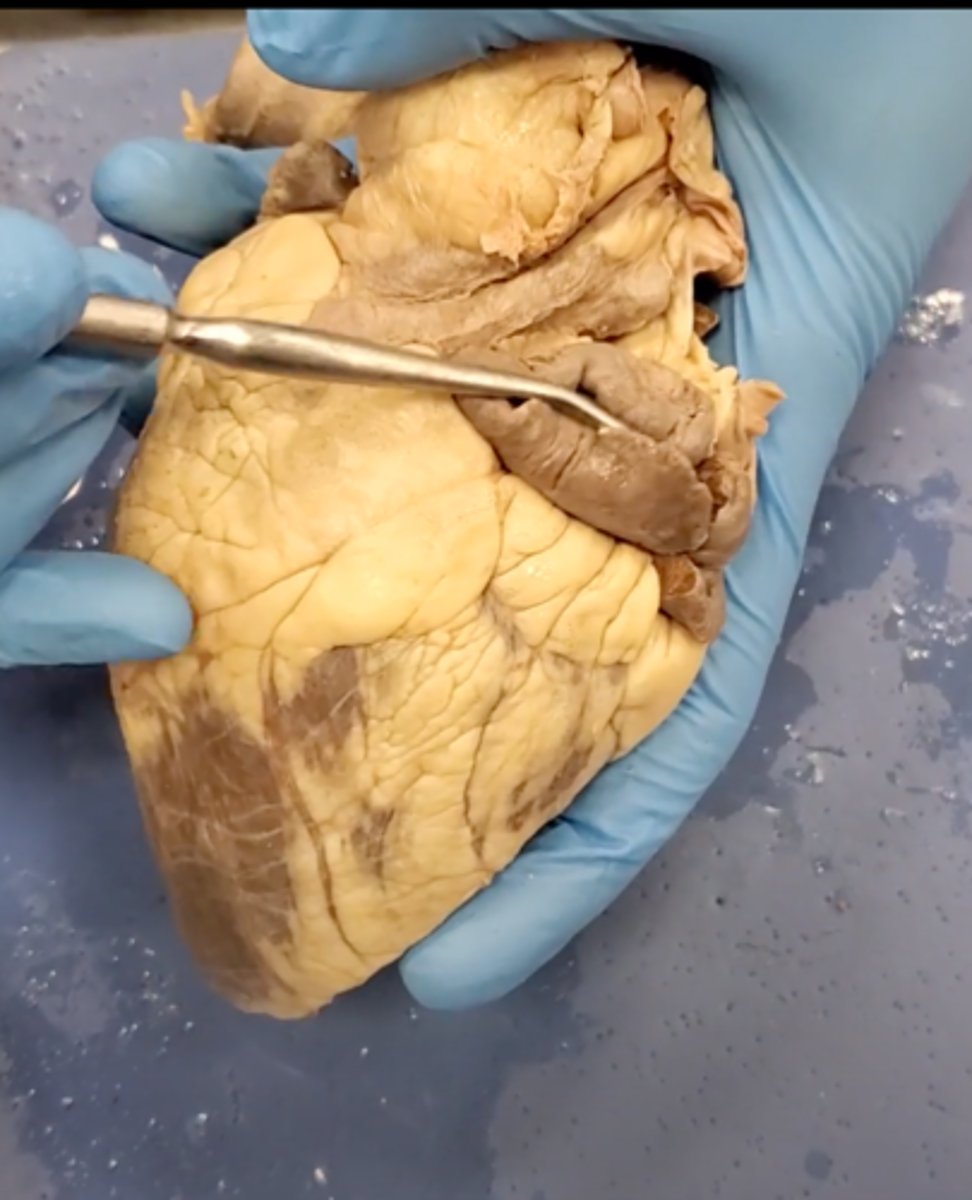

yellow sash of fat that tells you this if the front side of the heart (dissection)

pulmonary trunk (dissection)

t-shaped ribbon of fat on back side of heart (dissection)

left auricle (dissection)

right auricle (dissection)

left ventricle (dissection)

right ventricle (dissection)

right atrium (dissection)

left atrium (dissection)

bicuspid valve (dissection)

tricuspid valve (dissection)

aortic semilunar valve (dissection)

located between the left ventricle and the aorta

chordae tendineae (dissection)

thin bands of fibrous tissue that attach to the valves in the heart and prevent them from inverting